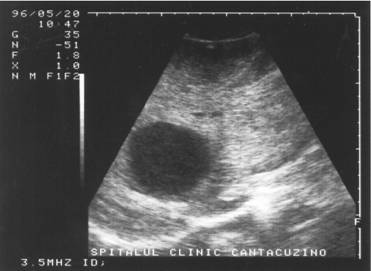

Figura 1. Vezica urinara

Figura 2. Chist renal stang situat in treimea medie

Figura 3. Chist ovar drept

Figura 4. Chist hepatic